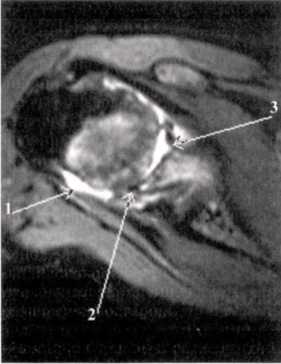

Ревматоидный артрит III стадия выпот в полости сустава (1), грубое эрозирование субхондрального слоя головки плечевой кости (2), фрагментация суставной губы гленоида.

Ревматоидный артрит, II ст. субхондральные жидкостные кисты в эпифизе плечевой кости (1), краевые узуры лучевой кости.

Ревматоидный артрит, III ст. субхондральные эрозии (1) и краевые узуры (2) дистального эпифиза плечевой кости, наличие суставного выпота (3) и массивная гипертрофия синовиальной оболочки (4).

Хронический продуктивно-пролиферативный синовит: гипертрофия синовиальных ворсин и формирование агрессивной грануляционной ткани - паннус. Пролиферация визуализируется в виде участков низкого или среднеинтенсивного МРС по Т2 и Т1, покрывающих поверхность заворотов, жировых ямок и капсулы сустава (от мелких неровных узелков до гомогенных слоистых отложений).

1. Плечевая кость, 2. локтевая кость, 3. лучевая кость